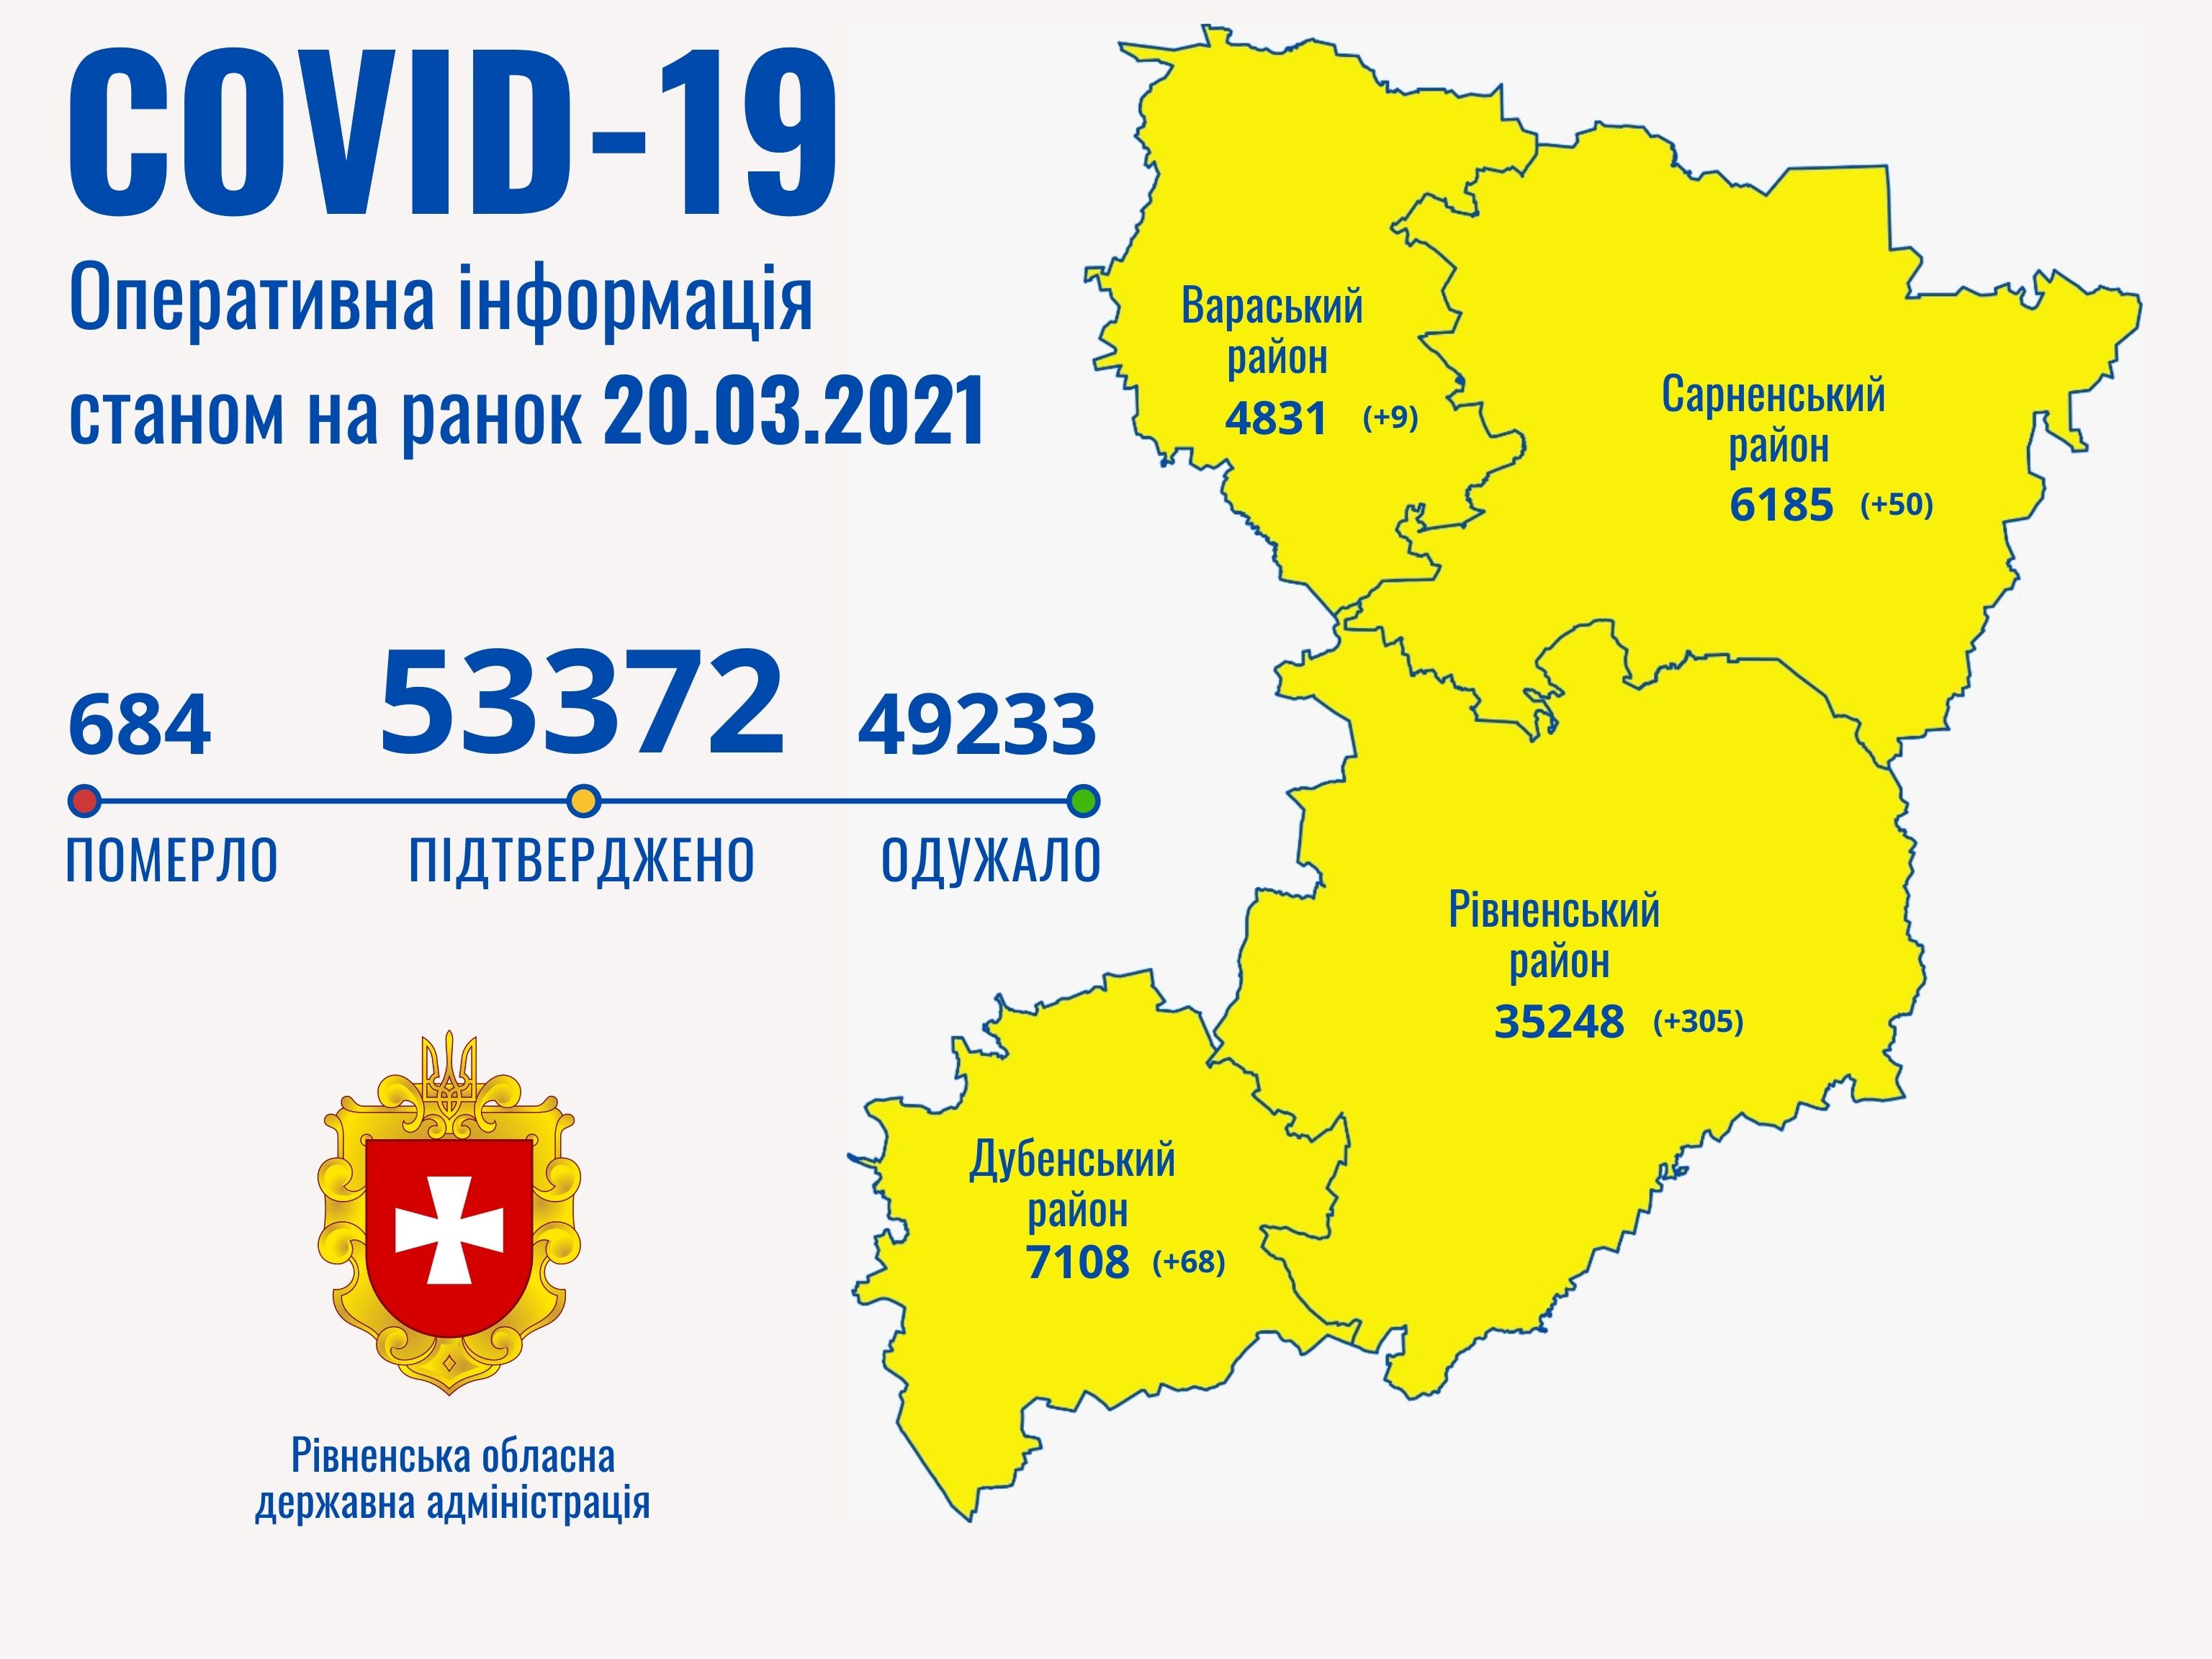

Коронавірус повертається: як стрімко зростає кількість хворих на Рівненщині (ВІДЕО)

Пів тисячі - у важкому стані, 9 жителів Рівненщини померли за добу від коронавірусу